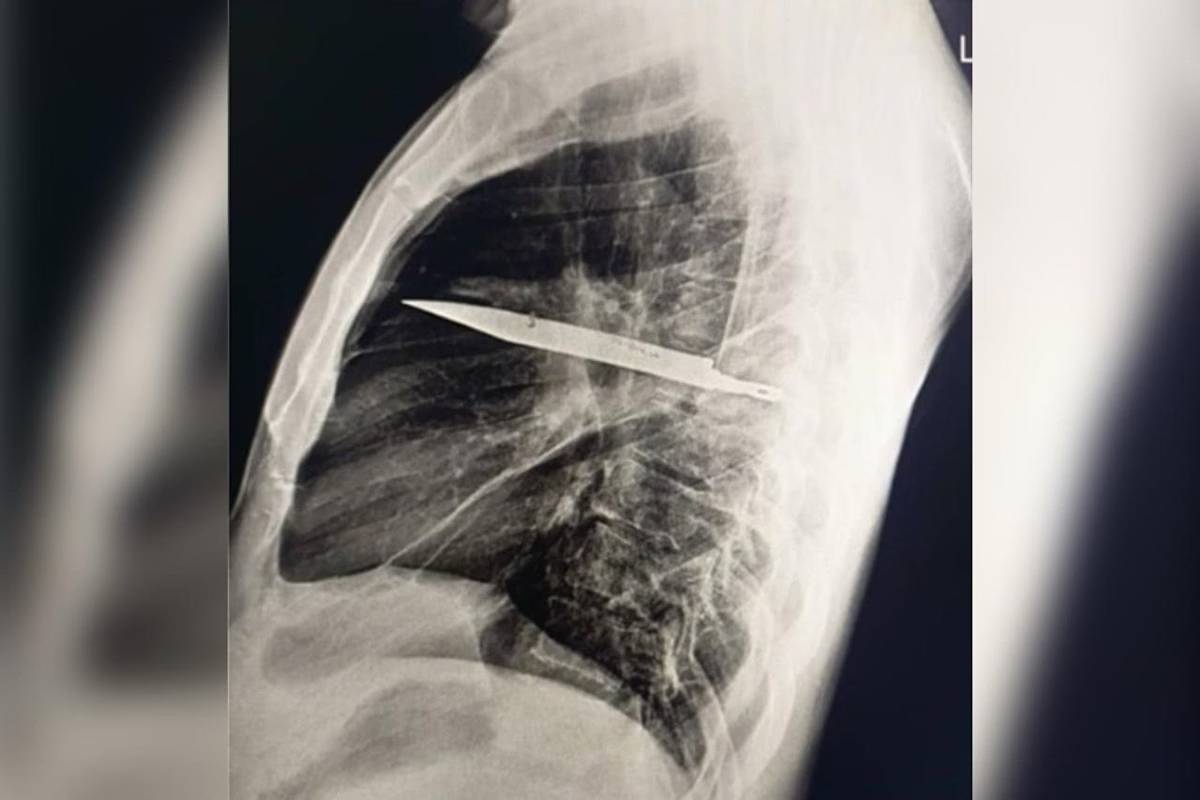

Surpresa no raio-x

O exame atual mostrou que uma lâmina estava presa ao lado direito do tórax, encostada à escápula. Apesar do tamanho, não atingiu órgãos vitais. Segundo os médicos, o acúmulo de pus foi causado pela presença do corpo estranho e por tecido danificado ao redor.